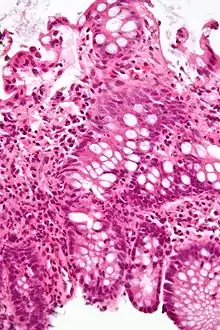

![]() Micrograph of the small intestine mucosa showing the intestinal glands - bottom 1/3 of image. H&E stain. | |

In histology, an intestinal gland (also crypt of Lieberkühn and intestinal crypt) is a gland found in between villi in the intestinal epithelium lining of the small intestine and large intestine (or colon). The glands and intestinal villi are covered by epithelium, which contains multiple types of cells: enterocytes (absorbing water and electrolytes), goblet cells (secreting mucus), enteroendocrine cells (secreting hormones), cup cells, tuft cells, and at the base of the gland, Paneth cells (secreting anti-microbial peptides) and stem cells.

Intestinal glands are found in the epithelia of the small intestine, namely the duodenum, jejunum, and ileum, and in the large intestine (colon), where they are sometimes called colonic crypts. Intestinal glands of the small intestine contain a base of replicating stem cells, Paneth cells of the innate immune system, and goblet cells, which produce mucus.[1] In the colon, crypts do not have Paneth cells.[2]